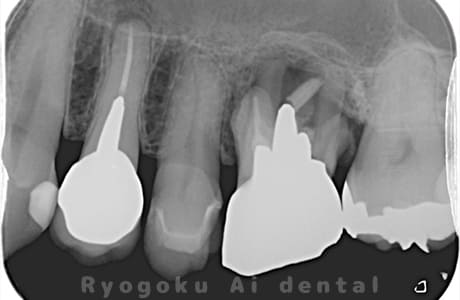

Case07

- 原因

- 右下6番歯根破折

-

- 治療内容

- インプラント治療

- 治療費用

- 約600,000円

右下の腫れが治らないとの事でご来院された患者様です。歯が割れていたため、抜歯を行い、骨に代わるお薬を入れ、インプラントを埋入致しました。経過良好で大変満足していただけました。

<リスク・副作用>

治療後、痛みや違和感、出血、腫れなどが出る事があります。喫煙者、糖尿病などの方の場合、歯が生着しない場合があります。